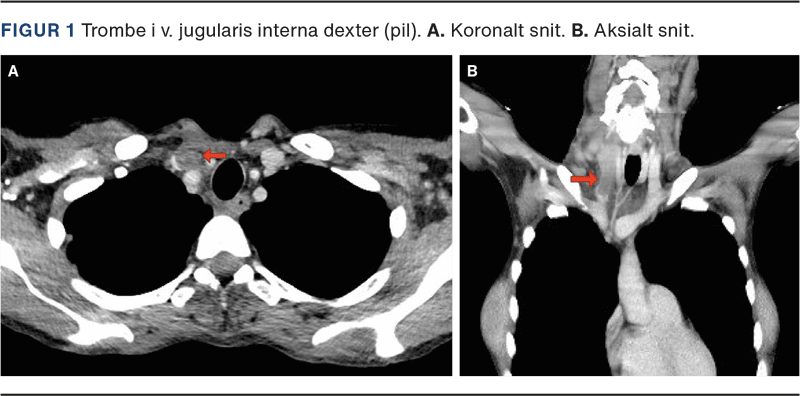

En 48-årig kvinde blev indlagt med kraftige halssmerter, diffus ømhed i nedre del af abdomen samt tiltagende svækkelse og påvirket almentilstand. Objektive fund var højrøde slimhinder i mundhulen og en 6 × 4 cm fast, øm udfyldning på højre side af halsen ved nederste tredjedel af m. sternocleidomastoideus. Patienten var febril (38,5 °C) med forhøjede infektionstal, leukocytter 14,1 × 109/l og et C-reaktivt proteinniveau på 93 mg/l. På formodning om bakteriel infektion blev der påbegyndt behandling med piperacillin/tazobactam. Bloddyrkning taget efter opstart af antibiotikabehandlingen var uden vækst af bakterier. På mistanke om LS blev der udført en CT af hals og thorax. CT’en viste en større trombe i VJI dexter (Figur 1), hvorfor det samlede sygdomsbillede var foreneligt med LS.